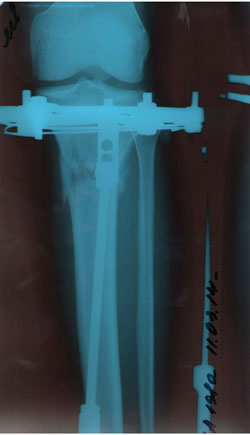

Рентген в 2 месяца.

Сращение отличное, снимать можно в первых числах апреля, но Н.Н. будет отсутствовать с 1 - 14 апреля. По этому, рекомендую приехать на снятие аппаратов 15 апреля (так будет лучше).